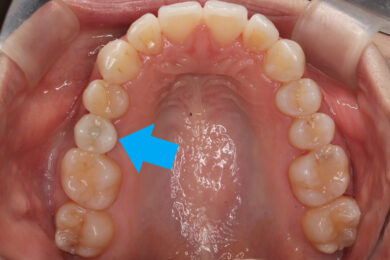

上部構造が入りました!

矢印の部分がインプラントの歯に当たる部分、上部構造です🦷

セラミックの中でも、最も強度のあるジルコニアセラミックでできています🦷🦷

取り付け方法は管理のしやすいスクリュー固定(スクリューリテイン)です。